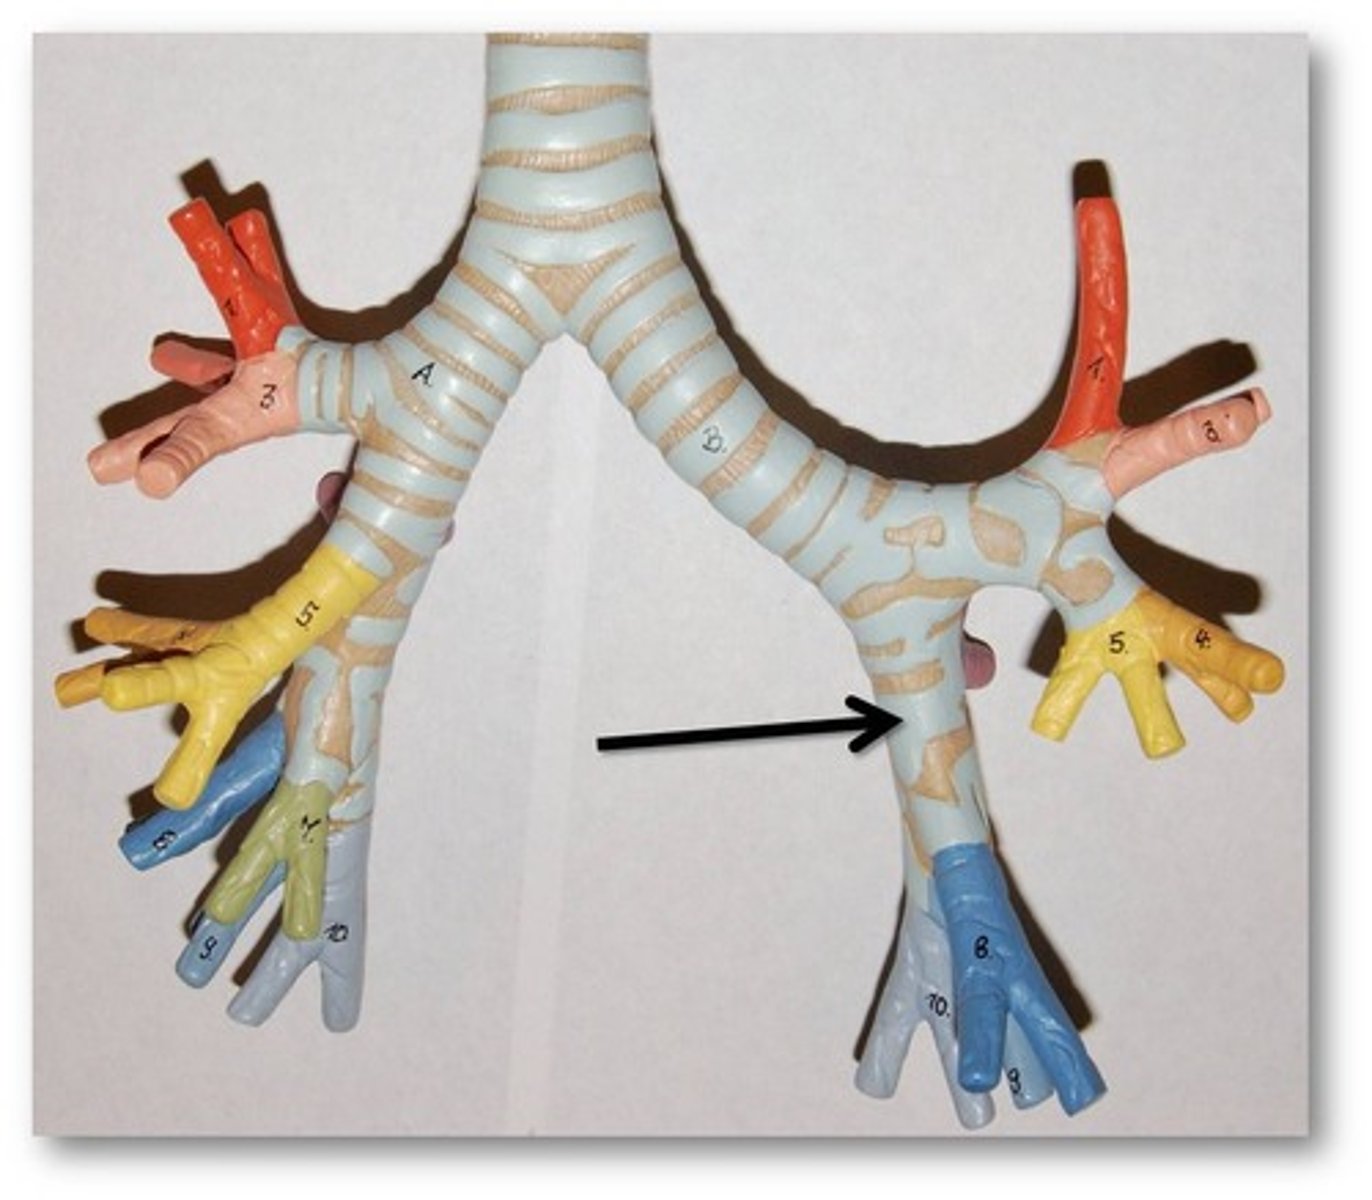

primary bronchus

The first branches of the trachea. There are two primary bronchi, one for each lung.

secondary (lobar) bronchus

The primary bronchi split into these smaller tubes within the lungs

tertiary (segmental) bronchus

branches of the secondary bronchi that divide into bronchioles; also called segmental bronchi

bronchial tree

collective name for the multiple branches of the bronchi and bronchioles of the respiratory system

bronchiole

branch of bronchi that are 1 mm or less in diameter and terminate at alveolar sacs